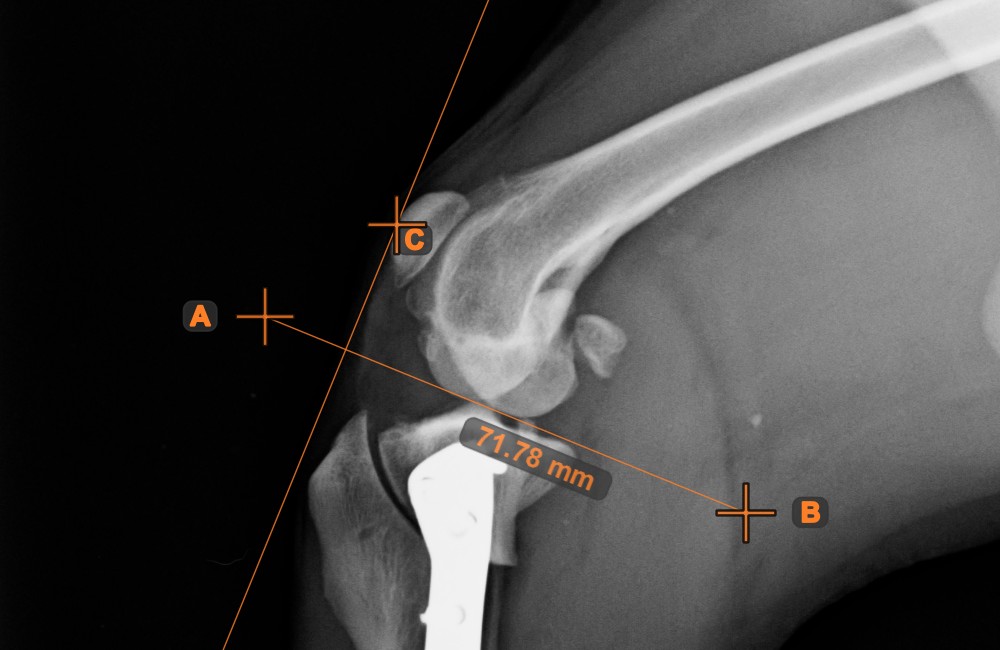

Line Measurement¶

Select the Line Measurement tool and assign it to one of the available mouse buttons. Place the start and end points on the scene or select them from already existing points on the image. The distance between the two points will be automatically

calculated by using the default calibration data, or the recalibrated data by the length calibration measurement.

Modify the start and end point by using the Select/Move Item tool. The distance between the two points will be automatically recalculated.

Center Point of Line¶

Identify and mark the center point of a new or existing line measurement on the scene by using the Center Point of Line tool.

Select the tool from the left toolbar and assign it to one of the available mouse buttons. Place the start and end points on the scene, select them from already existing points on the image, or select an already drawn line from the scene. The center point of the line will be automatically calculated and placed on the scene. The center point of each line will always be marked with the letter C.